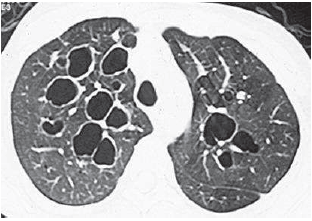

Observe a figura a seguir:

O diagnóstico é: